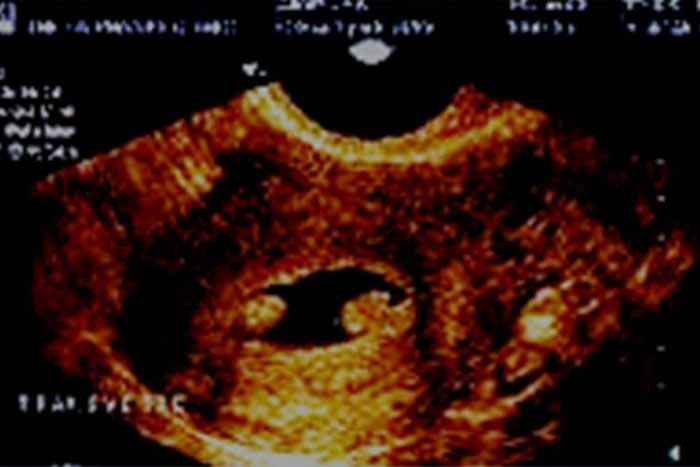

تخریب لایه بازال آندومتر بدنبال کورتاژ خشن و حاملگی پیشرفته و یا ابتلا به سل منجر به ایجاد اسکار و تشکیل باند فیبروتیک در داخل کاویته رحمی می شود. هیستروسونوگرافی به همراه روش سه بعدی 3D

مزایای زیادی در تشخیص چسبندگیها دارد تعیین محل دقیق چسبندگی در ارزیابی قبل از عمل جراحی از اهمیت زیادی برخوردار است. (1) چسبندگی معمولا بشکل باندهای فیبروتیک نازک و اکوژن که در عرض کاویته رحم کشیده شده اند، رویت می شود. نمای پاپیون شکل (bow-tie)در هیستروسونوگرافی نیز مشخصه چسبندگی داخل رحمی است. (7) .